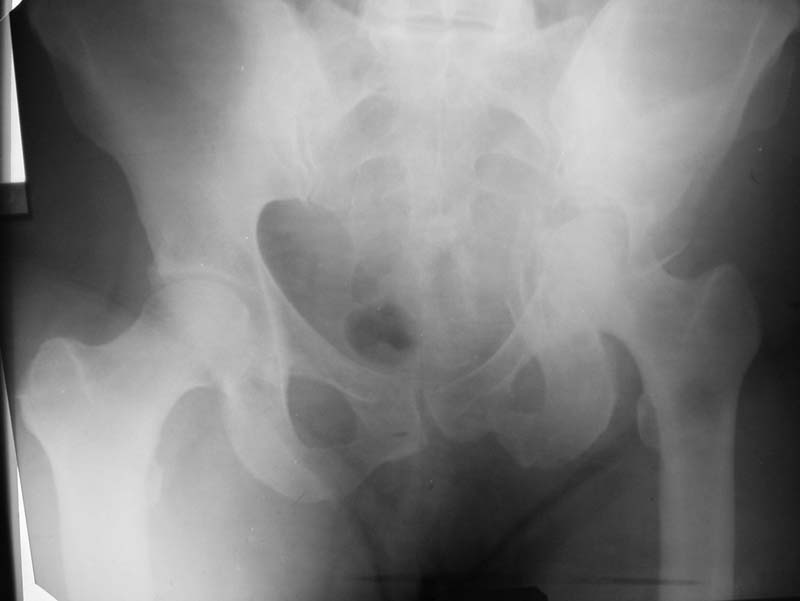

Женщина, 41 г.Травма 14.09. - падение с высоты. Имеется двухколонный перелом вертлужной впадины. Наш вариант лечения - открытая репозиция с внутренней фиксацией (пластина, винты), сначала открыть заднюю колону (доступом Кохером-Лангенбека с отсечением большого вертела), в случае необходимости перевести разрез в трехлучевой (для выхода на переднюю колонну). Возможно сразу применим трехлучевой доступ.Варианты лечения, выполнения операции?

По одной Р-грамме сложно принять решение о доступе. Колонны повреждены обе, а вот стенка вертлужной впадины повреждена только передняя\ косую подвздошную и косую запирательную проекции для уточнения.\ Из переднего подвздошно- павохового доступа осуществить репозицию и фиксащию передней и задней колонн, а так же передннего края вертлужной впадины реконструктивными пластинами и винтами. Этот доступ позволит решить проблемы в области крестцово-подвздошного сочленения, а они там есть. Задний и трех лучевой доступ будет полезен в случае повреждения задней колонны в сочетании с задней стенкой впадины.